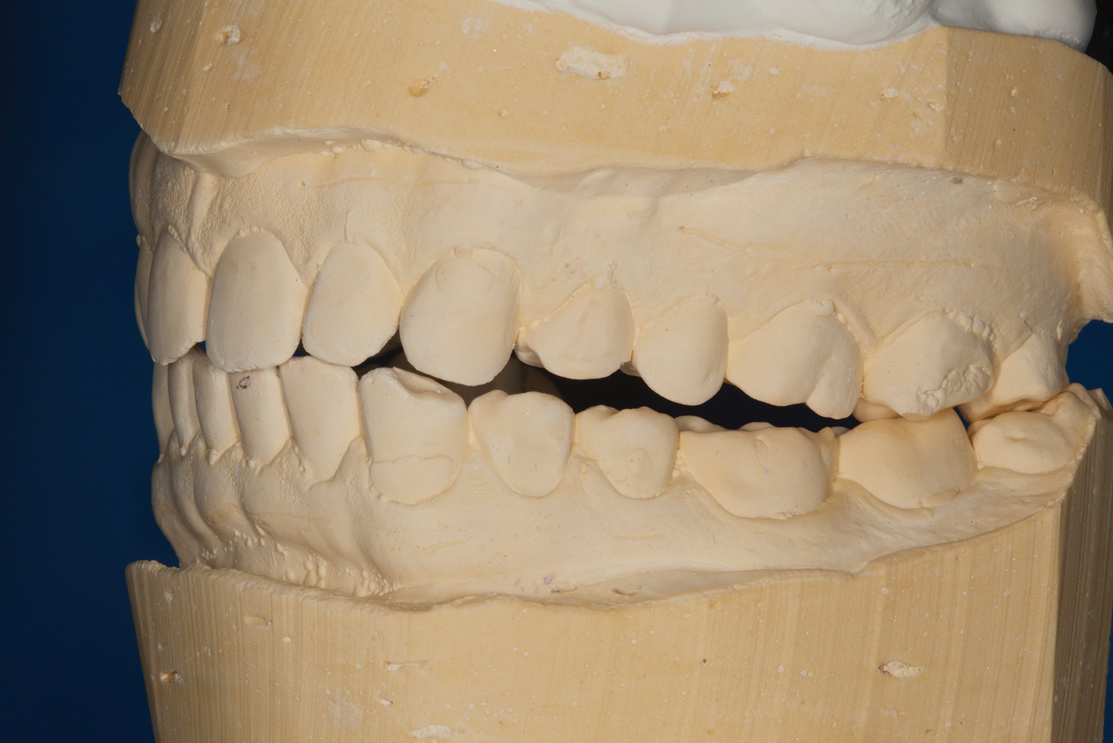

Fig 5. Mounted models showing maximum intercuspation.

Figure 5

Confirmed by the mounted models (Figure 5), the patient's bite was obviously unsatisfactory, but with the orthotic in place, he was completely symptom-free and stable, and therefore, considered to be in acceptable function. However, he was considered to be in occlusal dysfunction without it because he lacked simultaneous, equal-intensity posterior contacts.